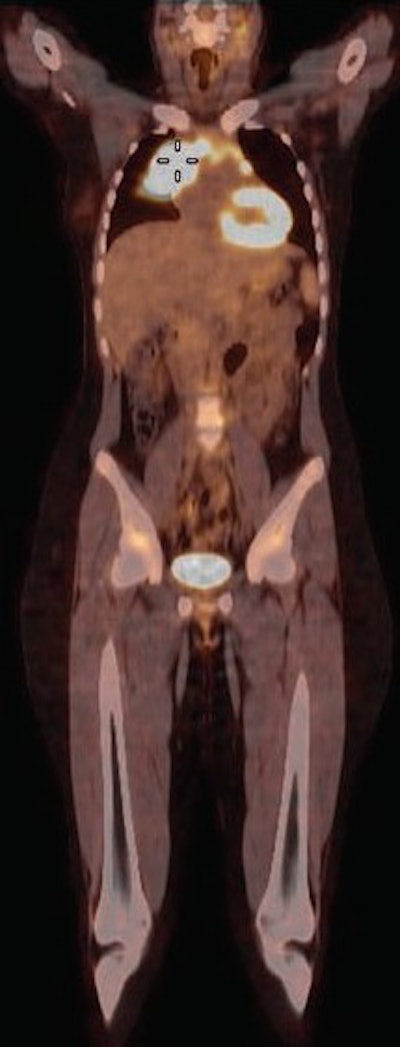

FDG-PET/CT of a 15-year-old girl with a mediastinal mass who was a candidate for biopsy and histopathologic investigation. The coronal fused PET/CT indicates an FDG-avid tumor (cursor) in the mediastinum. Image courtesy of AJR.

FDG-PET/CT of a 15-year-old girl with a mediastinal mass who was a candidate for biopsy and histopathologic investigation. The coronal fused PET/CT indicates an FDG-avid tumor (cursor) in the mediastinum. Image courtesy of AJR.Forty-five subjects were imaged on a 16-slice PET/CT scanner (Gemini GXL, Philips Healthcare) in the supine position with normal respiration. Whole-body imaging began 60 minutes after injection of 5.2 MBq/kg of body weight of FDG, up to a maximum of 370 MBq (10 mCi).